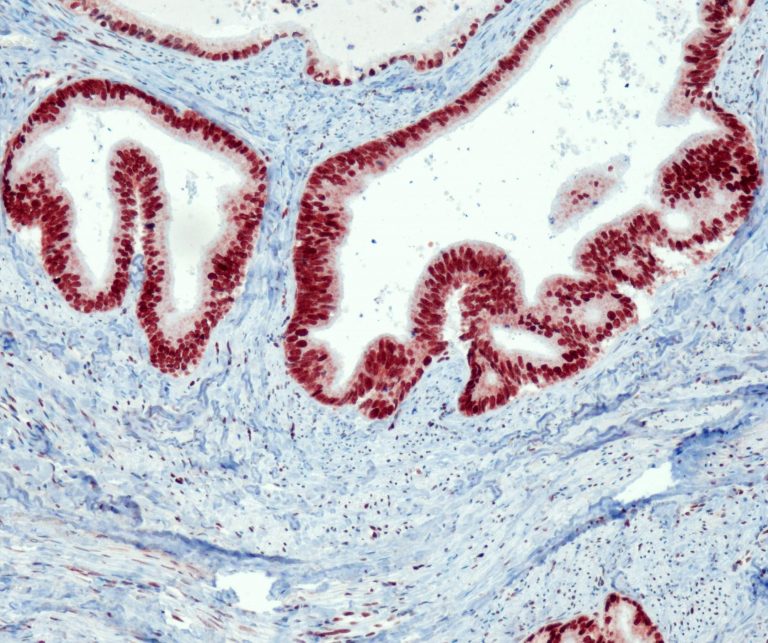

Gynecological Pathology

Breast Pathology